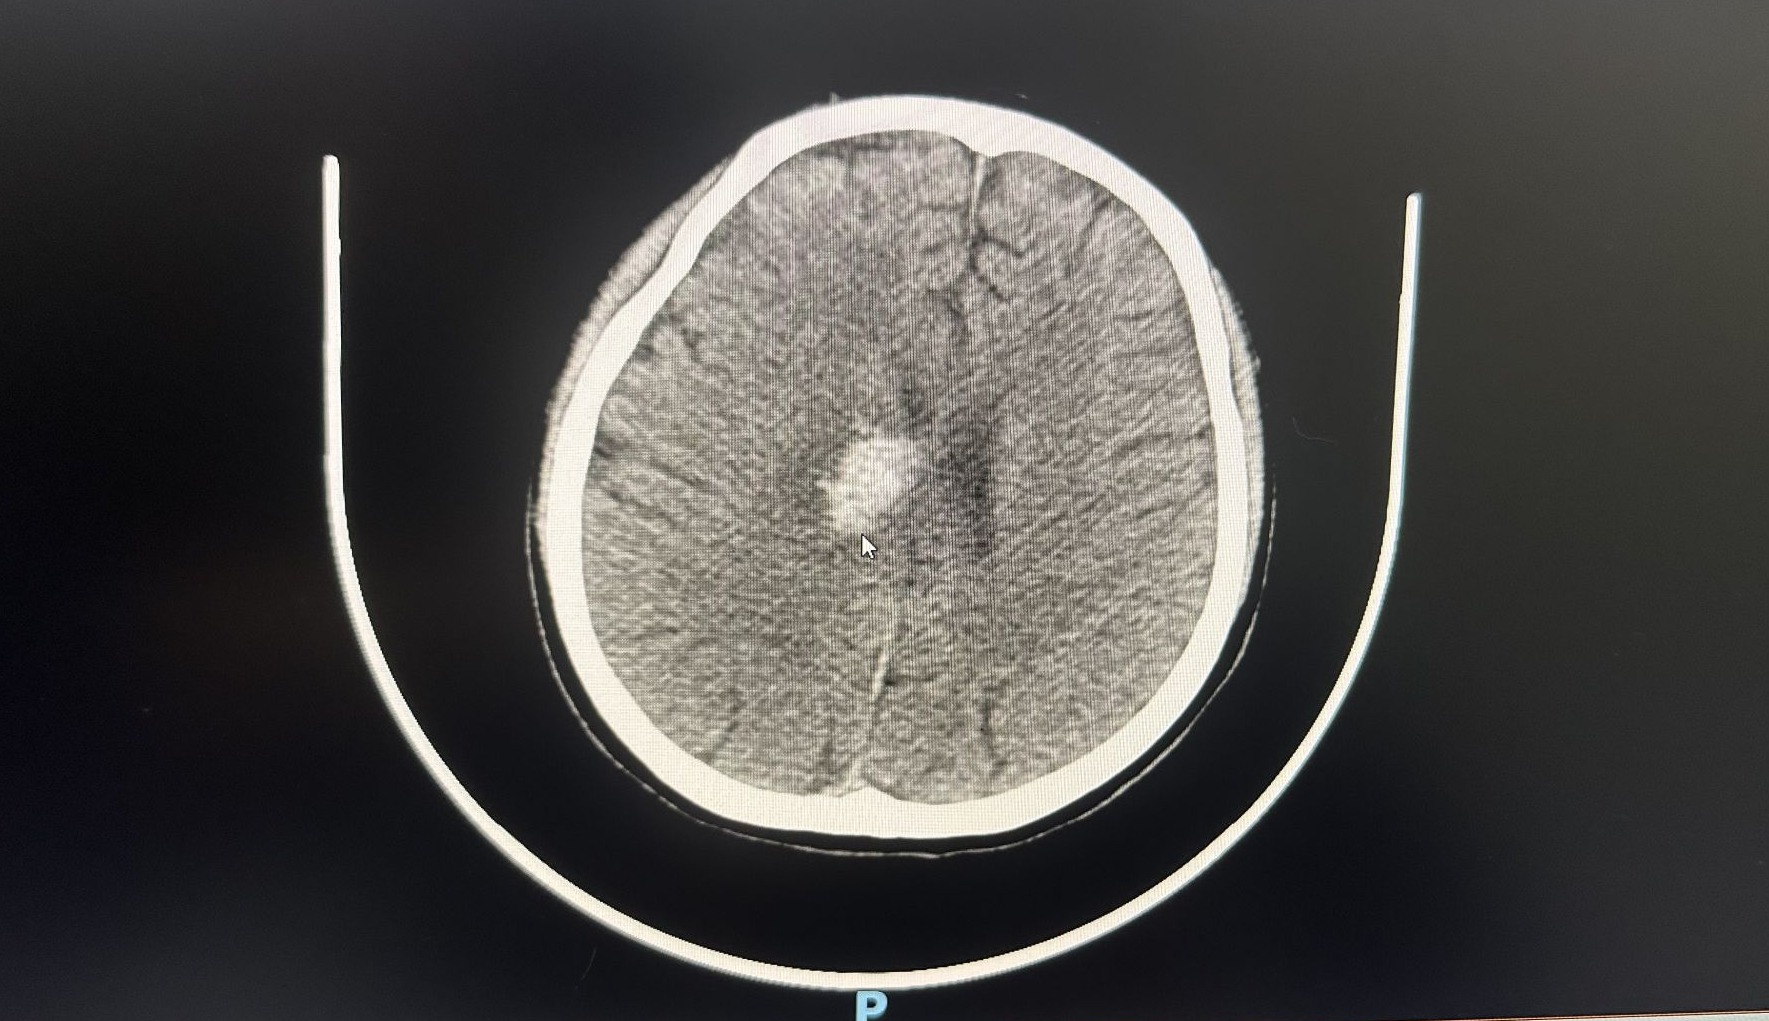

转入ICU,意味着另一场更为复杂的持久战刚刚开始。患者入院后,医疗团队立即为她完善了包括头颅CT、CTA(CT血管成像)在内的全面检查,排除如脑血管瘤等可能导致心搏骤停的颅内病变。

检查结果提示小吴存在蛛网膜下腔出血,这为治疗增加了新的难度——团队必须在维持生命体征的同时,严密防控脑出血的加重。

患者脑出血的CT影像,白色为出血区域。